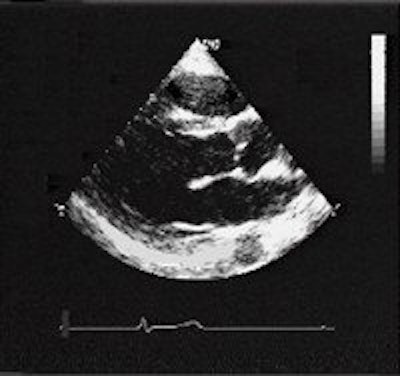

![]() |

| Seventeen-year-old asymptomatic basketball player. Rest ECG was normal except for rare ventricular escape beats, singled and coupled. Two-dimensional transesophageal echocardiography (TEE) of the left parasternal short-axis aortic view. Panel B (below) clearly shows the right coronary artery (RCA) originating abnormally from the left sinus of the Valsalva, close to the left coronary ostium and the left main (LM), and running around between the aorta and pulmonary artery; for comparison, panel A (above) shows the normal position of coronary ostia in a 16-year-old water polo player. |